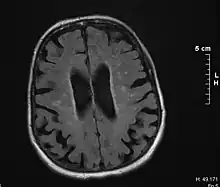

Binswanger's disease can usually be diagnosed with a CT scan, magnetic resonance imaging, and proton magnetic resonance spectrography in addition to clinical examination. Indications include infarctions, lesions, or loss of intensity of central white matter and enlargement of ventricles, and leukoaraiosis. A mini–mental state examination has been created to quickly assess cognitive impairment and serves as a screening test for dementia across different cultures.[13]

Imaging

Leukoaraiosis refers to the imaging finding of white matter changes that are common in Binswanger disease. However, leukoaraiosis can be found in many different diseases and even in normal patients, especially in people older than 65 years of age.[5]

There is controversy whether leukoaraiosis and mental deterioration actually have a cause and effect relationship. Research has shown that different types of leukoaraiosis can affect the brain differently, and that proton magnetic resonance spectroscopy would be able to distinguish the different types more effectively and better diagnose and treat the issue.[9] Because of this information, white matter changes indicated by magnetic resonance imaging or computerized tomography cannot alone diagnose Binswanger disease, but can aid to a bigger picture in the diagnostic process. There are many diseases similar to Binswanger's disease including CADASIL syndrome and Alzheimer's disease, which makes this specific type of white matter damage hard to diagnose.[5] Binswanger disease may be diagnosed by a team of experts including a neurologist and psychiatrist to rule out other psychological or neurological problems.[3] Because doctors must successfully detect enough white matter alterations to accompany dementia as well as an appropriate level of dementia, two separate technological systems are needed in the diagnosing process.

Much of the major research today is done on finding better and more efficient ways to diagnose this disease. Many researchers have divided the magnetic resonance imaging of the brain into different sections or quadrants. A score is given to each section depending on how severe the white matter atrophy or leukoaraiosis is. Research has shown that the higher these scores, the more of a decrease in processing speed, executive functions, and motor learning tasks.[14][15] Other researchers have begun using computers to calculate the percentage of white matter atrophy by counting the hyper-intense pixels of the magnetic resonance images. These and similar reports show a correlation between the amount of white matter alterations and the decline of psychomotor functions, reduced performance on attention and executive control.[16][17] One type of technology is called susceptibility weighted imaging (SWI) which is a magnetic resonance technique which has an unusually high degree of sensitivity and can better detect white matter alterations.[18]